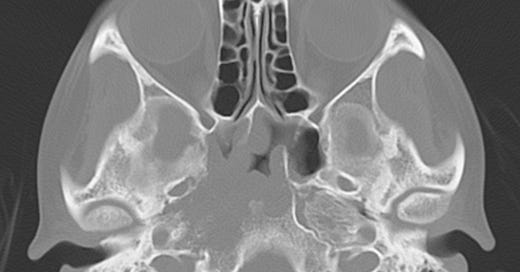

Nasopharyngeal carcinoma. A right sided soft tissue mass has eroded the petrous apex, right lateral clivus, and right lateral sphenoid sinus. Coronal postgadolinium T1-weighted image shows the large, enhancing right nasopharyngeal mass invading the clivus and right cavernous sinus and encasing the right cavernous internal carotid artery.